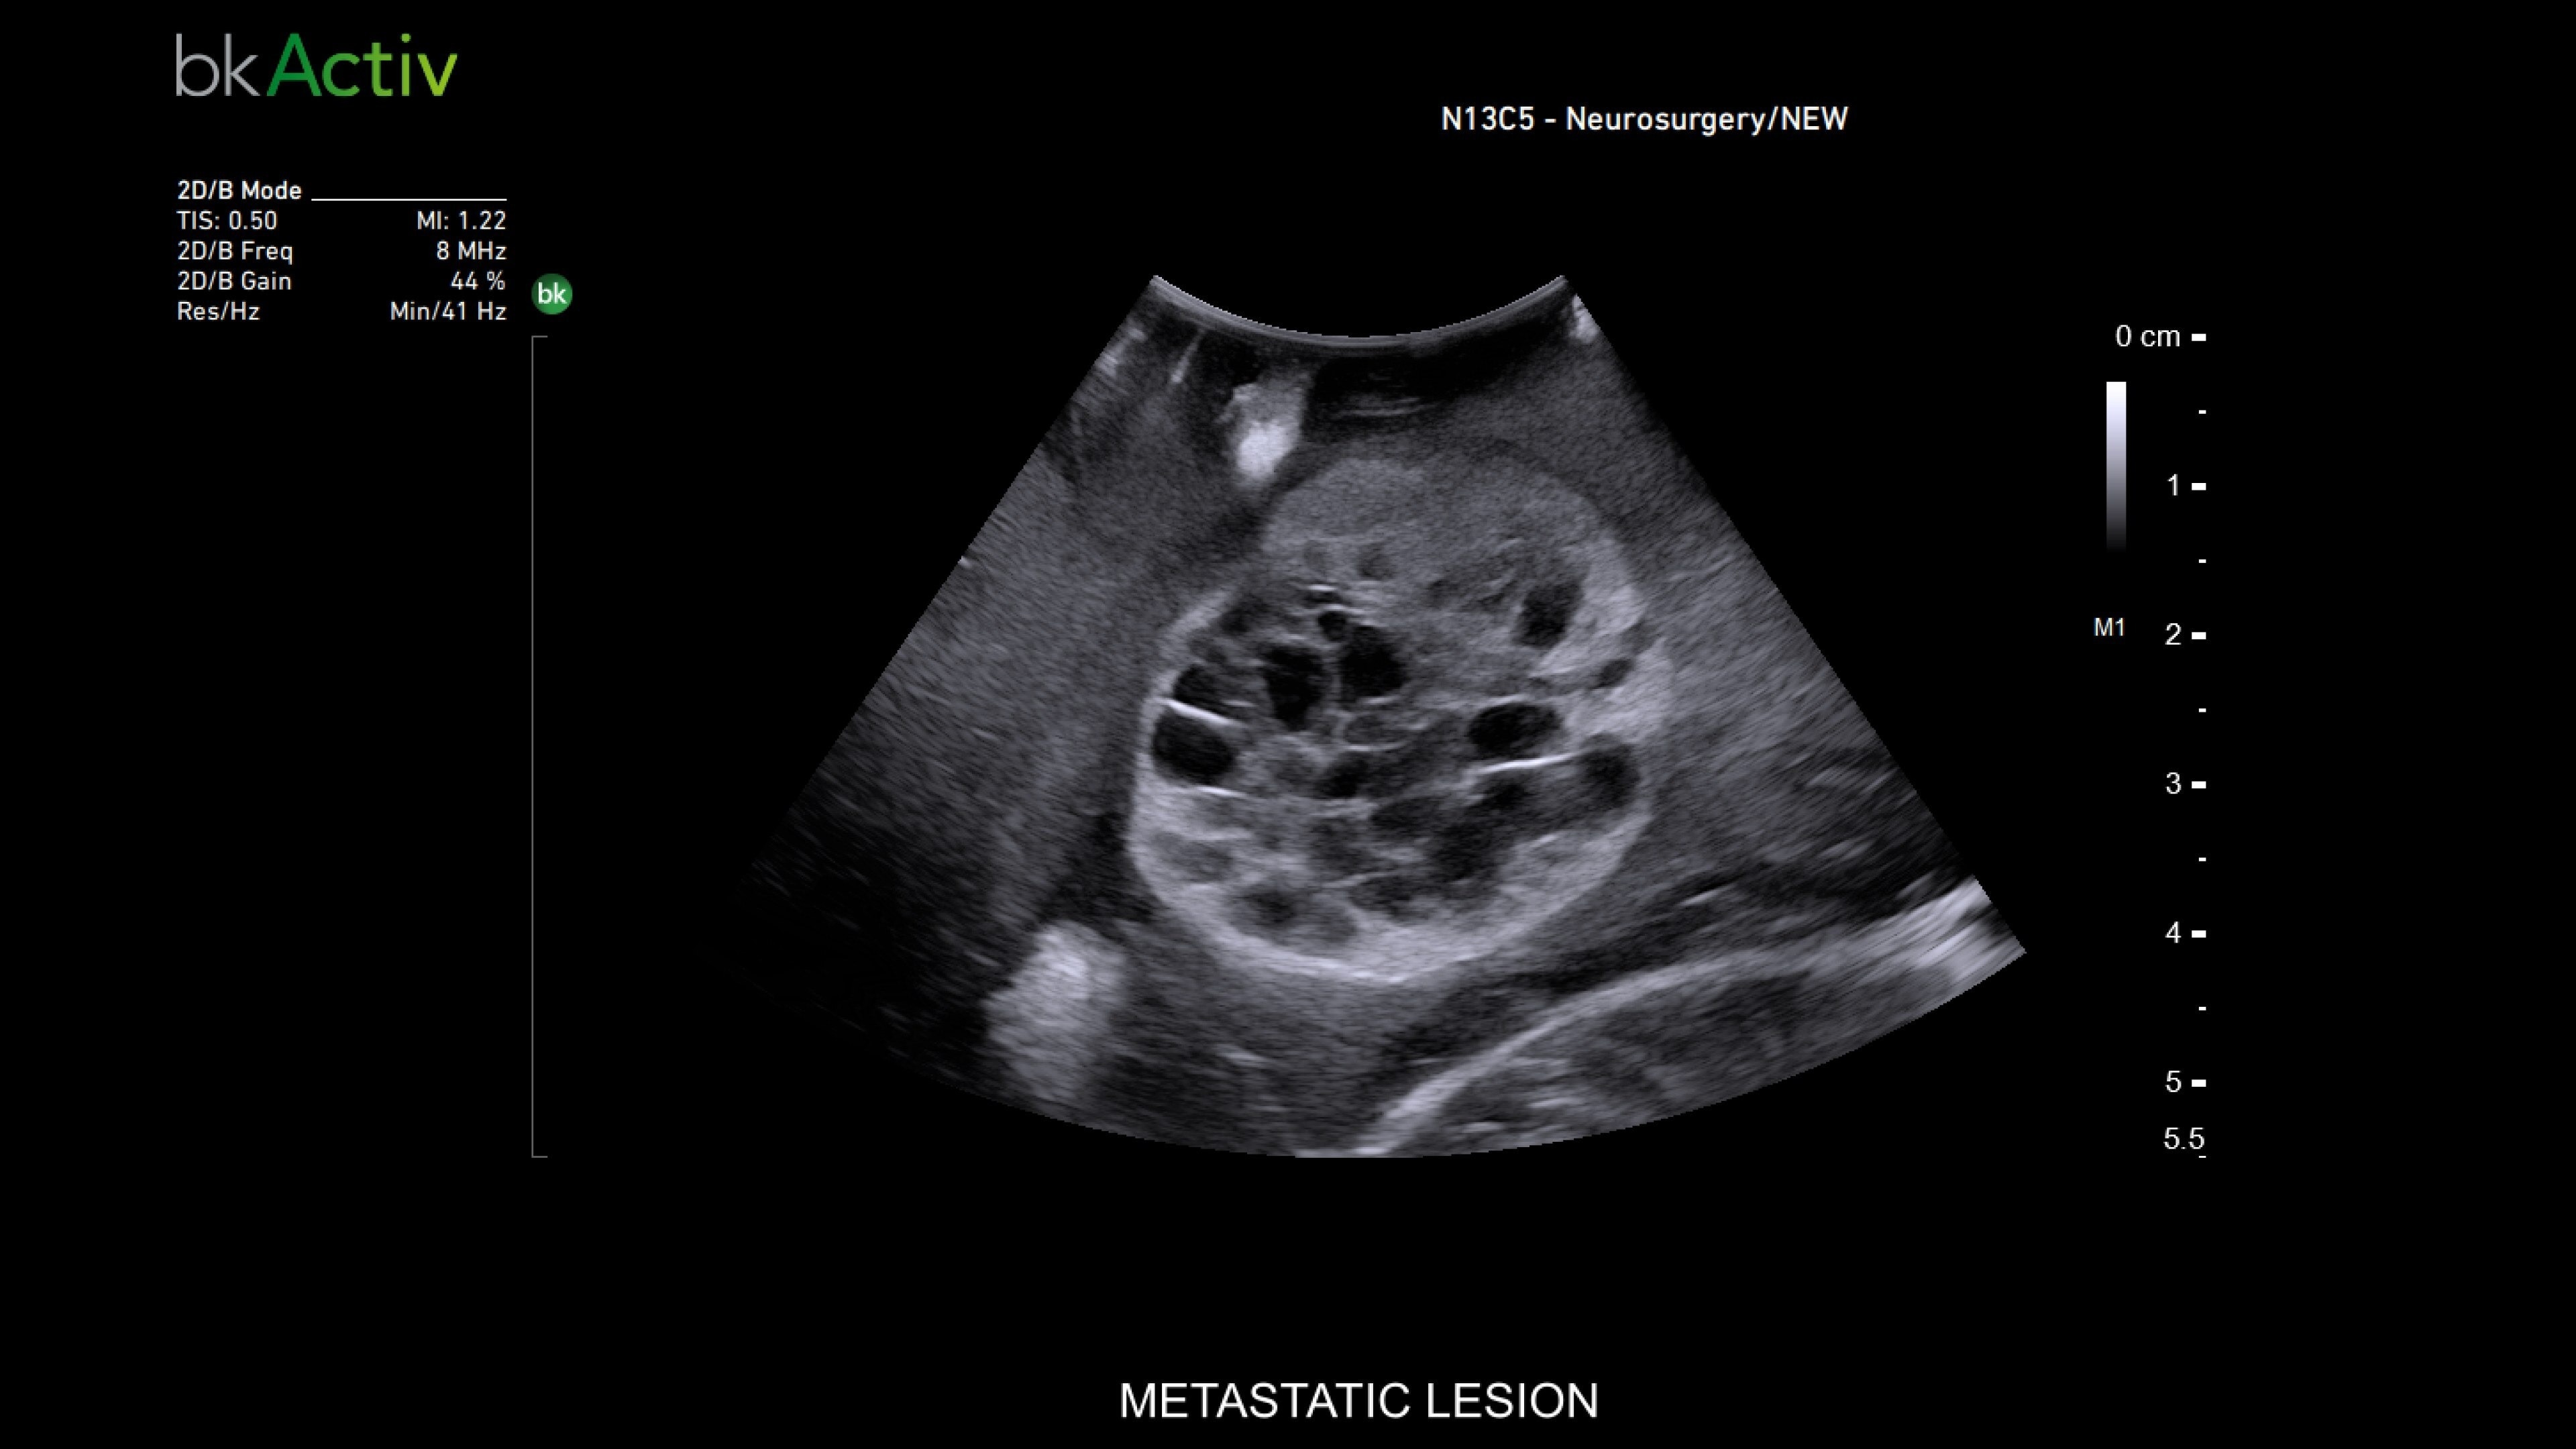

Advanced imaging for neurosurgery

The bkActiv ultrasound system provides real-time imaging for neurosurgery and spine procedures. Its improved algorithms offer uniform image resolution, greater detail around lesion borders, and enhanced penetration. The system includes specialized transducers, such as the N13C5 craniotomy transducer for deep penetration and the N20P6 minimally invasive transducer* for accessing hard-to-reach areas. The Smart Button™ technology allows neurosurgeons to control images within the sterile field, ensuring precision during complex procedures.